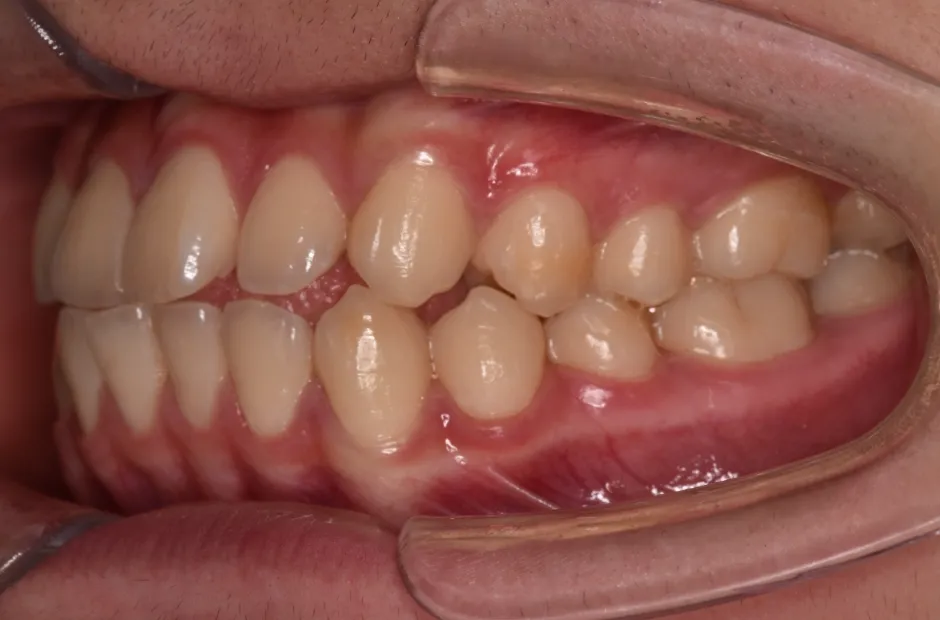

出っ歯

| 診断名・主訴 | 出っ歯 |

|---|---|

| 年齢・性別 | 16歳・男性 |

| 治療期間・回数 | 1年4か月 |

| 治療に用いた主な装置 | ブラケット |

| 抜歯部位 | 上顎4,4 |

| 治療費 | 60万円(税抜) |

| リスク・副作用 | 装置による違和感・疼痛・歯肉退縮・歯根吸収・虫歯のリスクなど |

治療前